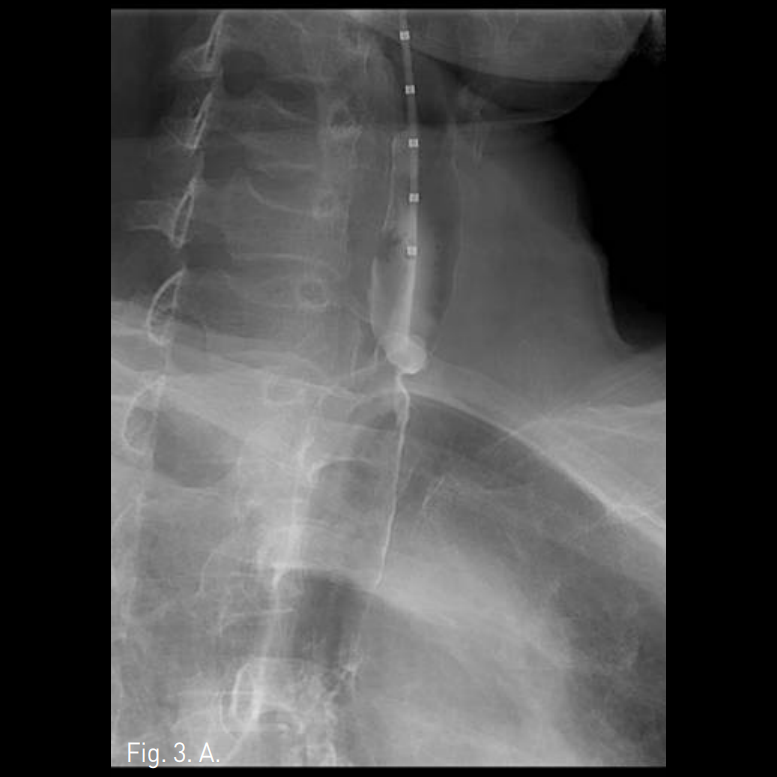

Fig. 3

A-C. Successful luminal dilatation was done using 15mm and 20mm balloon catheters.